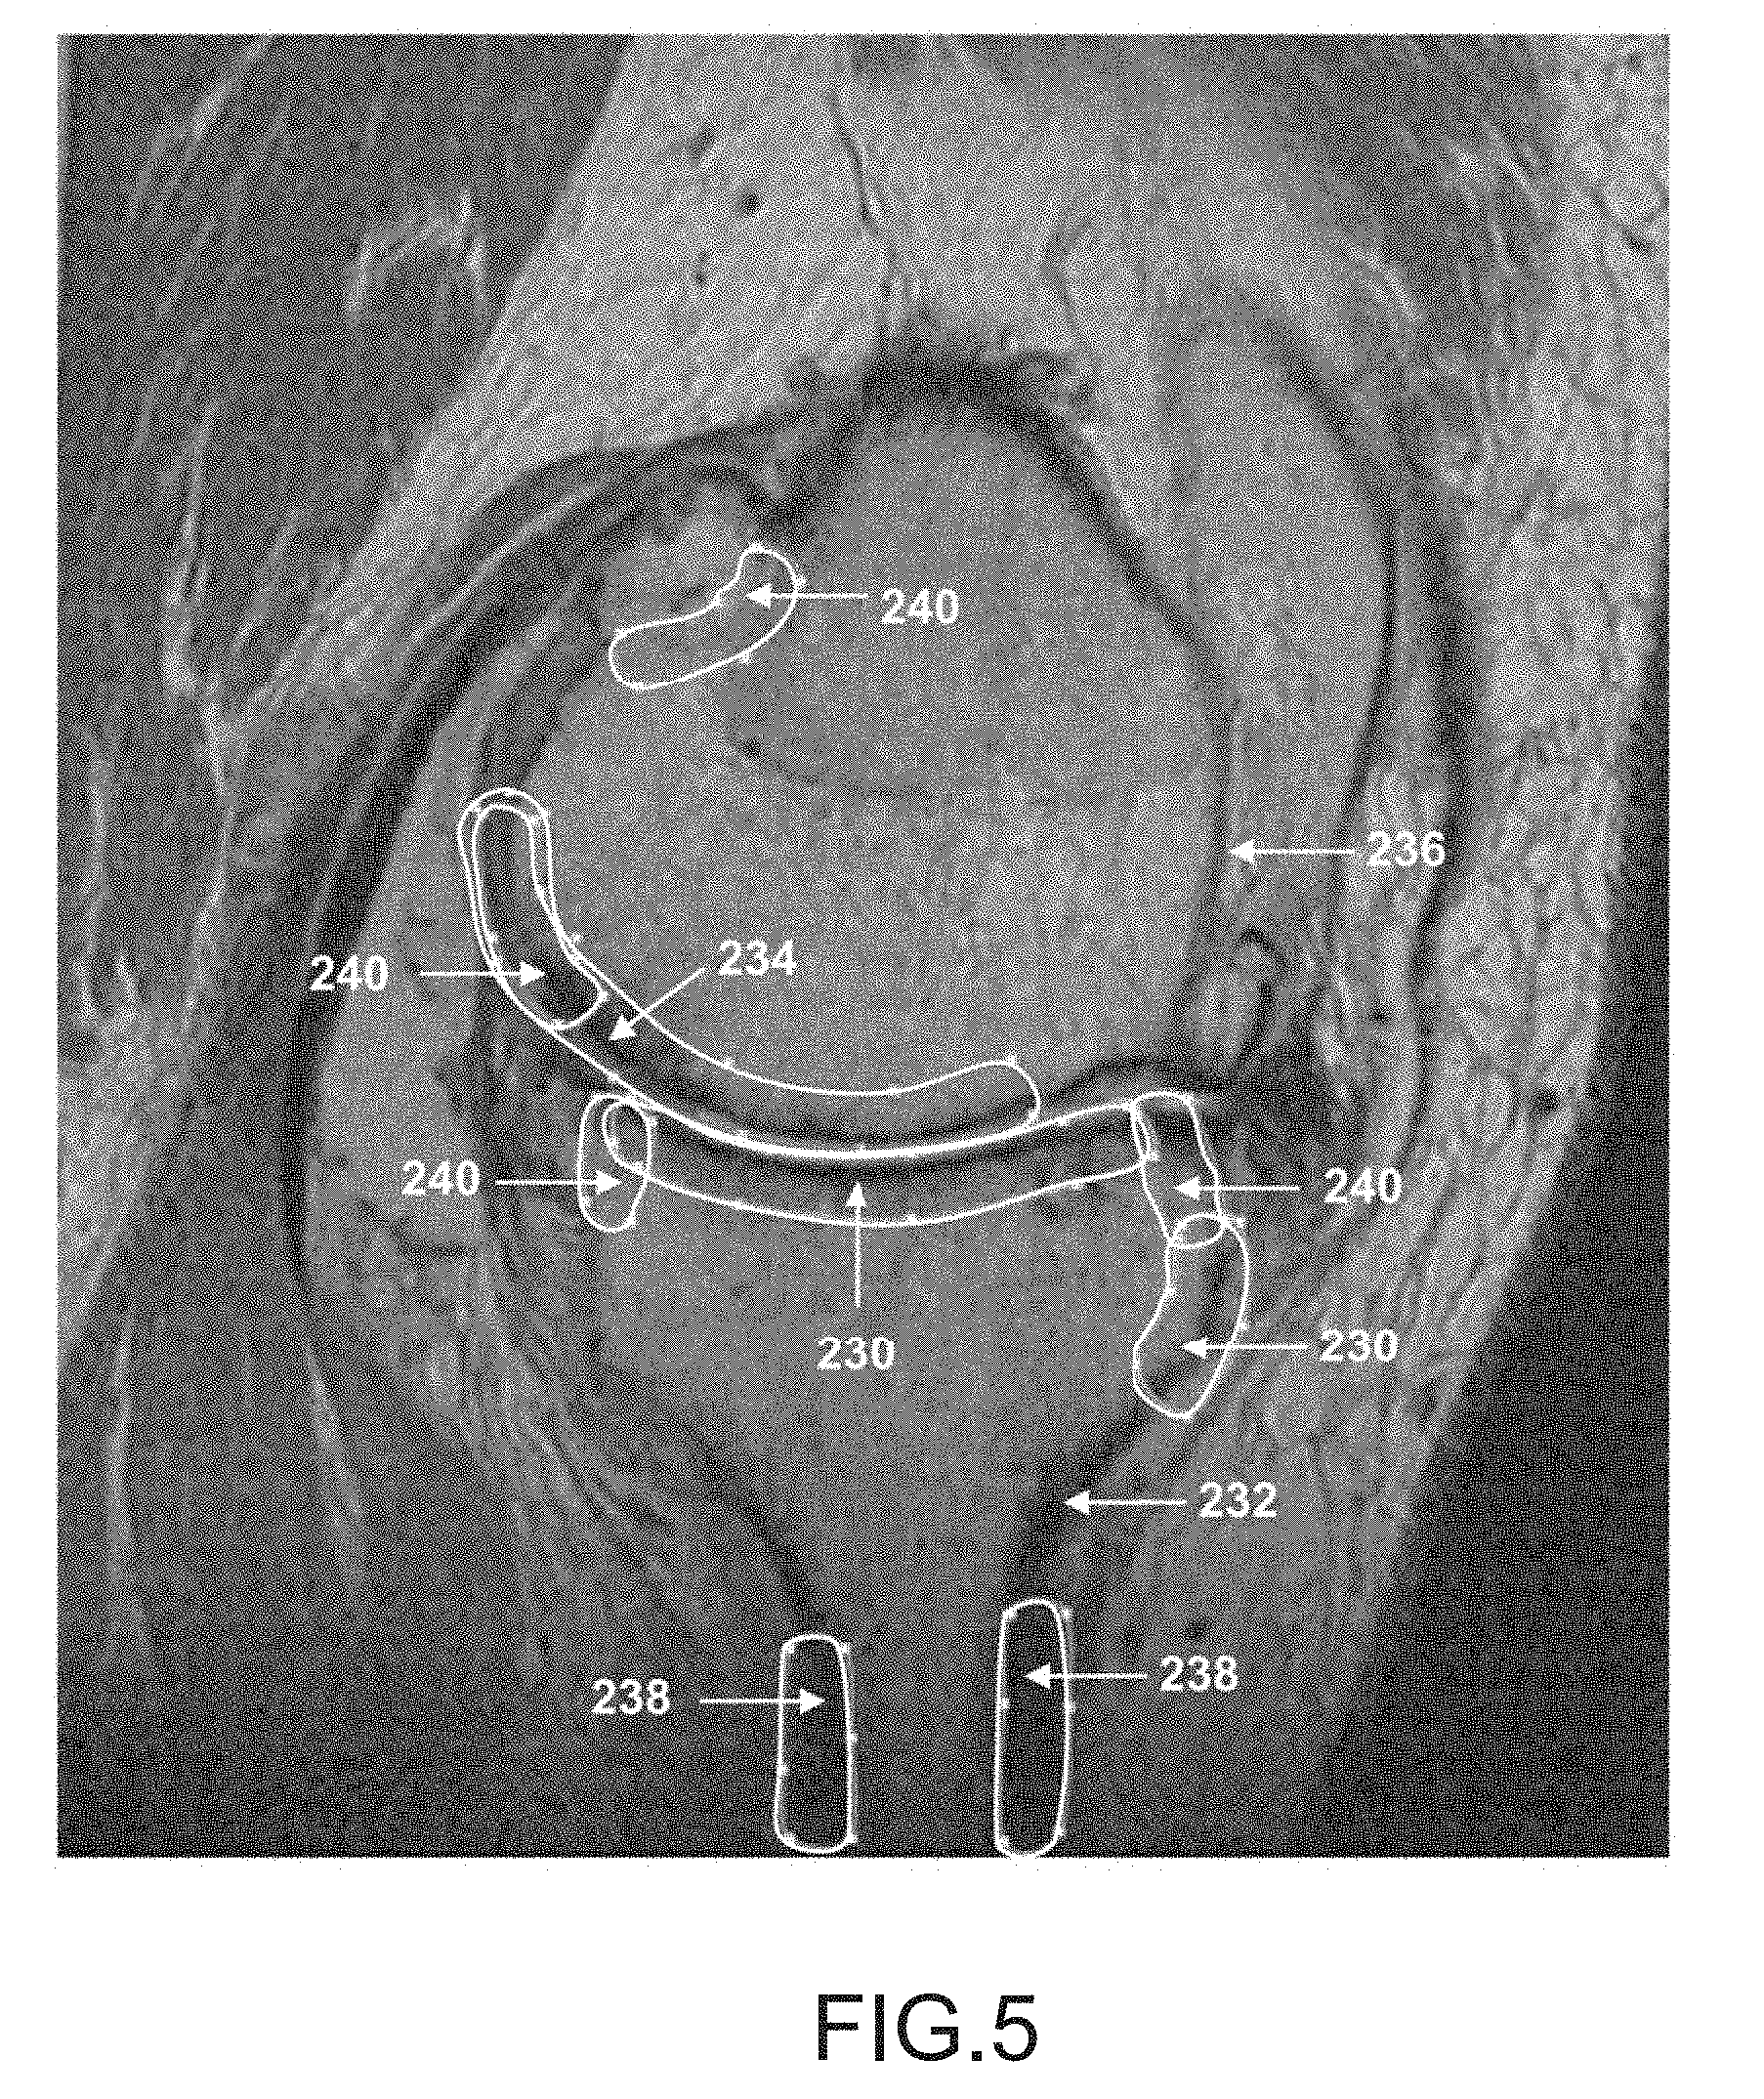

FIG. 5 is a sagittal plane image slice of a femur and tibia depicting regions where good definition may be needed during automatic segmentation of the femur and tibia.

FIG. 5 depicts a MRI scan slice that illustrates image regions where good definition may be needed during automatic segmentation of the image. Typically, this may be areas where the bones come in contact during knee motion, in the anterior shaft area next to the joint and areas located at about a 10- to 30-millimeter distance from the joint. Good definition may be needed in regions 230 of the tibia 232 and regions 234 of the femur 236. Regions 238 depict areas where the tibia is almost tangent to the slice and boundary information may be lost due to voxel volume averaging.

[0159]

Voxel volume averaging may occur during the data acquisition process when the voxel size is larger than a feature detail to be distinguished. For example, the detail may have a black intensity while the surrounding region may have a white intensity. When the average of the contiguous data enclosed in the voxel is taken, the average voxel intensity value may be gray. Thus, it may not be possible to determine in what part of the voxel the detail belongs.

[0160]

Regions 240 depict areas where the interface between the cortical bone and cartilage is not clear (because the intensities are similar), or where the bone is damaged and may need to be restored, or regions where the interface between the cancellous bone and surrounding region may be unclear due to the presence of a disease formation (e.g., an osteophyte growth which has an image intensity similar to the adjacent region).